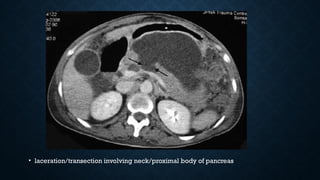

CT FINDINGS

• laceration/transection involving neck/proximal body of pancreas

CT FINDINGS • 40% of pancreatic injuries may not be visible on CT in first 12 hrs

• laceration/transection involvingneck/proximal body of pancreas